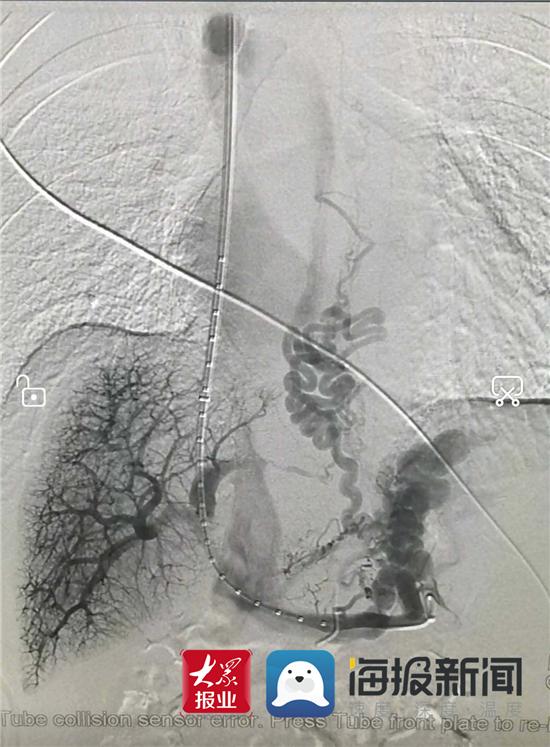

手术图像

经颈静脉入路成功建立右肝静脉-门静脉左支分流道,造影可见多条粗大的曲张静脉团

植入支架后分流道通畅,曲张静脉消失

介入科专家团队经过充分的术前准备,历经两个小时,为患者成功施行了“经颈静脉肝内门体分流术”。术中先穿刺颈静脉,引入穿刺器械至肝静脉,再经肝静脉穿刺门静脉成功后,将支架放置于肝实质内,支架两端分别置于门静脉和肝静脉内,实现门静脉血流直接经支架分流道向下腔静脉分流,降低了门静脉压力,术中成功栓塞了曲张的胃冠状静脉-食管静脉丛,术后造影显示原异常分流的胃底、食管曲张静脉丛已闭塞消失,支架分流道血流通畅。